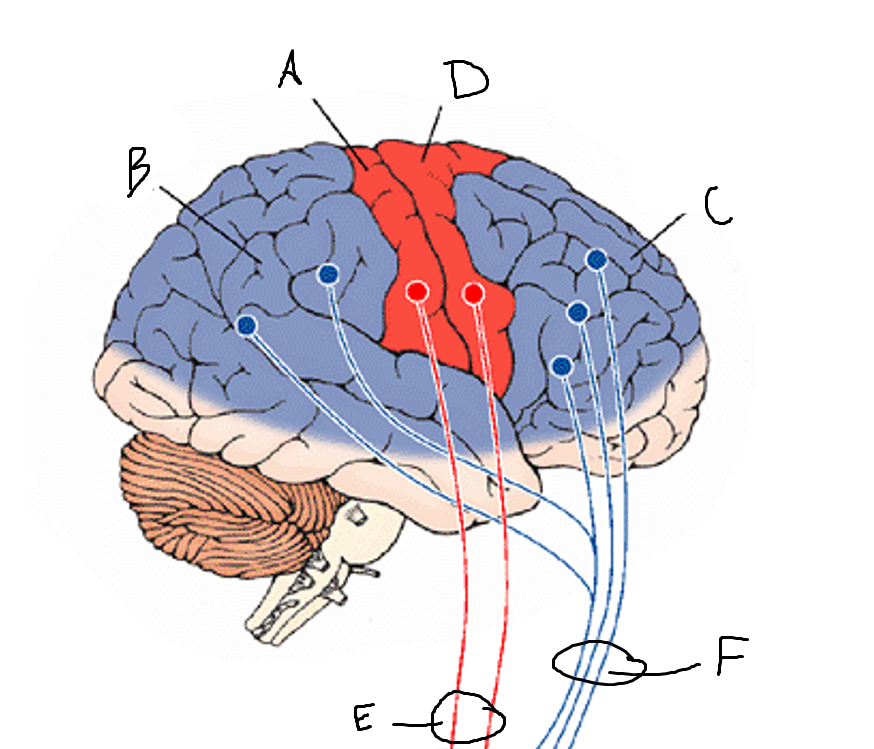

basal ganglia

A

somatosensory cortex

B

parietal association cortex

C

frontal and prefrontal cortices

D

primary motor cortex

E (where are the projections?)

putamen

F (where are the projections?)

caudate